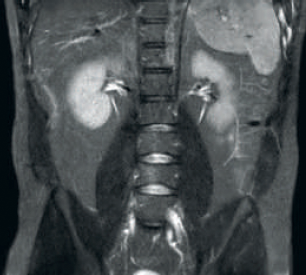

Maggiore coerenza e migliore qualità dell'immagine La tecnologia di ricezione RF dStream digitalizza il segnale RM direttamente nella bobina RF, con un aumento fino al 40% del rapporto segnale-rumore* in tutto il volume dell'immagine. Semplificazione del flusso di lavoro e aumento della produttività La bobina posteriore integrata nel piano portapaziente elimina la manipolazione delle bobine nel 60% degli esami. Le bobine anteriori leggere e adattabili e la possibilità di connettere la bobina con un singolo cavo e una sola mano ne rendono più facile l'uso.

L'Hennepin County Medical Center (HCMC) gestisce una struttura di risonanza magnetica all'avanguardia utilizzando lo scanner RM Philips Ingenia 1.5T, con tecnologia dStream.*